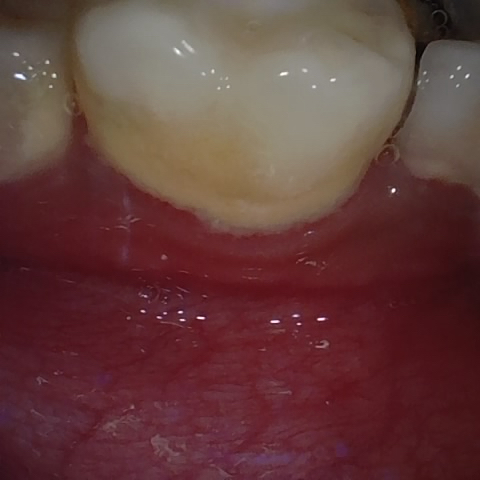

Incorrect Quality Level

The reference annotation for this image is

None

.

Please select the correct quality level.

Annotated as "Good"